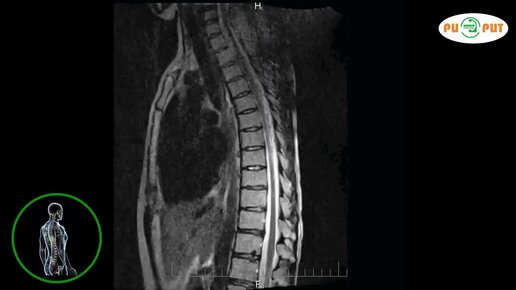

Что покажет МРТ трех отделов позвоночника